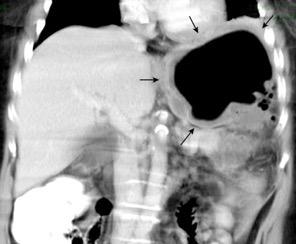

Nódulos pulmonares múltiples. (flechas verdes). Masas paratraqueales. (flechas amarillas). Dudoso ensanchamiento retrocrural (flechas negras). sigue….

Ttawfik A et al. Trans-diaphragmatic Pathologies: Anatomical Background and Spread of Disease on cross-sectional Imaging. Current Problems in Diagnostic Radiology. 2021.

T. mixto de células germinales del testículo

izquierdo Metástasis pulmonares. (flechas verdes). Ganglios paratraqueales. (flechas amarillas). Ganglios retroperitoneales (flechas negras)

Tawfik A et al. Trans-diaphragmatic Pathologies: Anatomical Background and Spread of Disease on cross-sectional Imaging. Current Problems in Diagnostic Radiology. 2021.